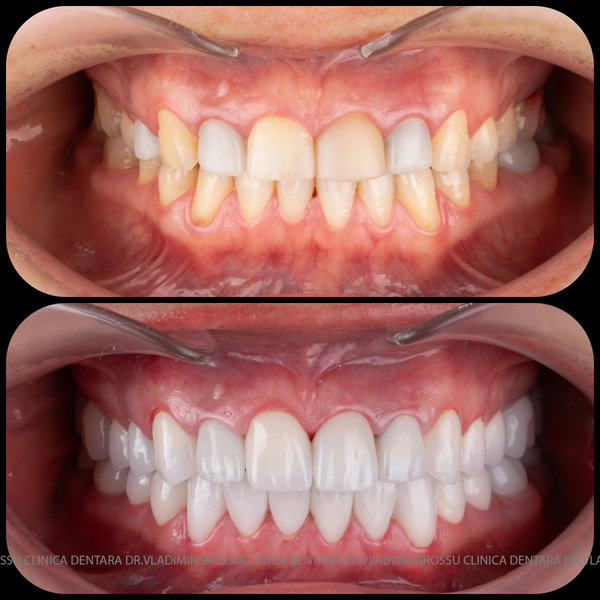

Caz 1

Caz 2

Transformările estetice și impactul reabilitării asupra vieții pacienților

Reabilitarea dentară produce o schimbare vizibilă și profundă în aspectul pacientului, cu efecte pozitive evidente asupra stimei de sine și a calității vieții. Mulți pacienți relatează bucuria redobândirii funcției masticatorii și dispariția complexelor legate de aspectul dentar.